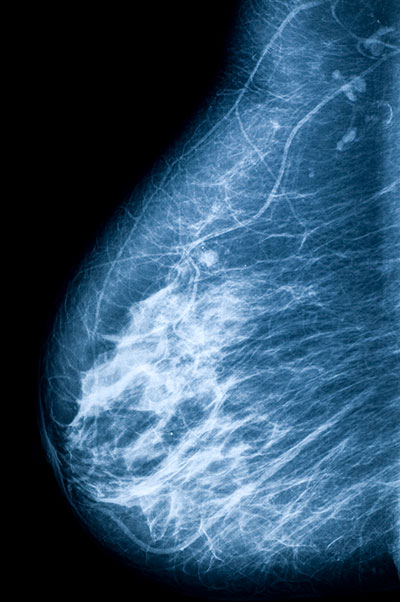

Breast cancer scan